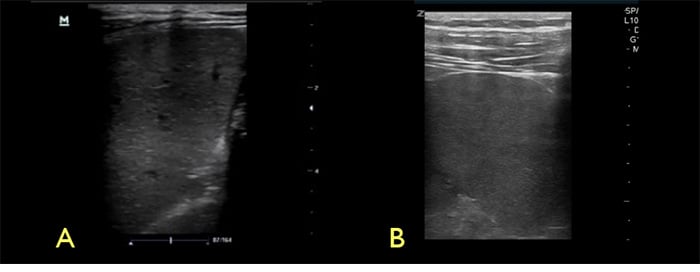

Figure 4. Spleen with low frequency (A) vs high frequency (B) transducers